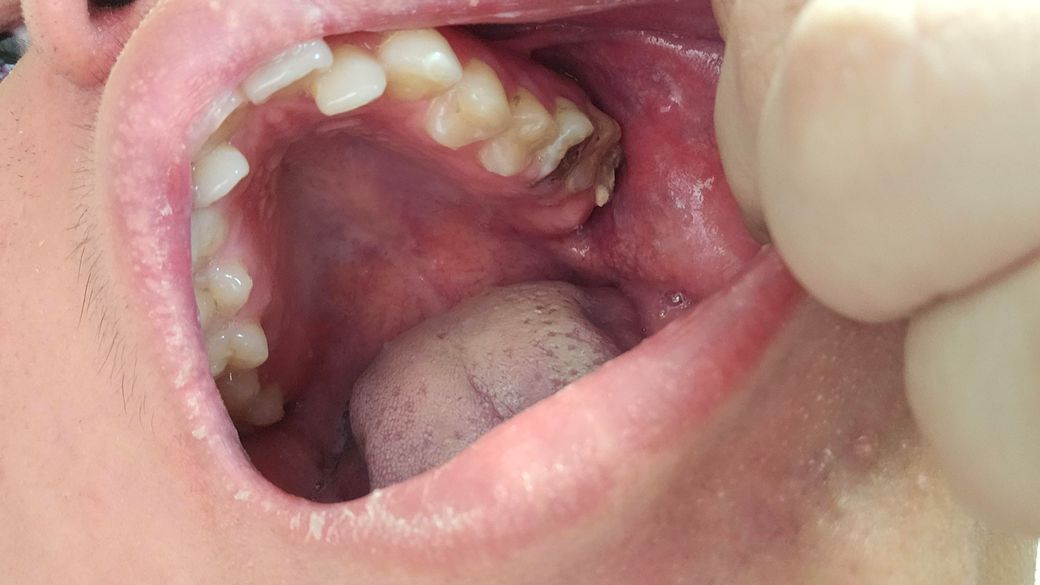

제가 다음주토요일11월9일 치과 갔는데요 조금 늦게 갔는것가요 다음주 토요일 치과 예약 꼭해야하는것가요? 늦게갔도 치료할수있나요 제이빨상태가상태이면

• 2번 째 사진

이미치아 상태가 안좋기 때문에 2주 후에 간다고 해서 치료 방법에 크게 차이가 날 것 같진 않습니다.

육안상으로 아래 치아는 발치를 하셔야될것같지만 위쪽 치아는 엑스레이를 찍어보고 치료를 할지 발치를 할지 결정해야될것같습니다.

치아에ㅐ 이미 충치가 많이 진행된것으로 보입니다.

빠른 치료가 필요할것으로 보이기 때문에 가능한 빠른 시간내에 치과에서 진료를 받아보는것이 좋습니다.

치과는 당일 진료가 어려울 수 있습니다. 예약 반드시 하세요. 발치 가능성 있는 치아들입니다.